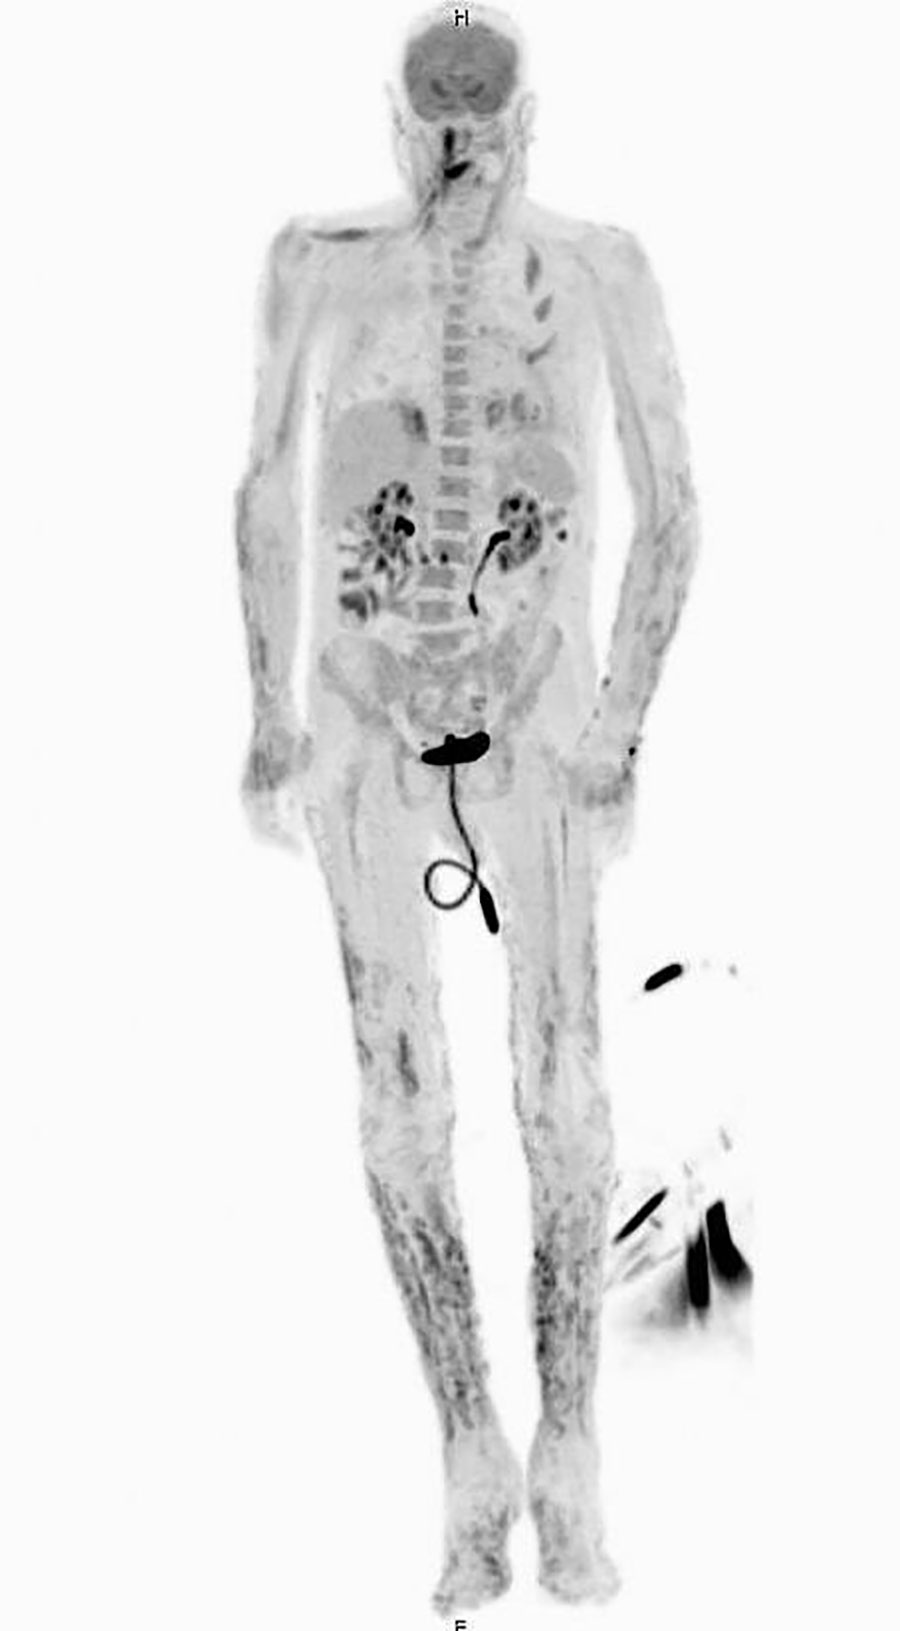

Figure 2. Positron emission tomography/computed tomography showing innumerable widespread 18F-fluorodeoxyglucose avid cutaneous and subcutaneous lesions that developed in a patient with disseminated Acanthamoeba infection.